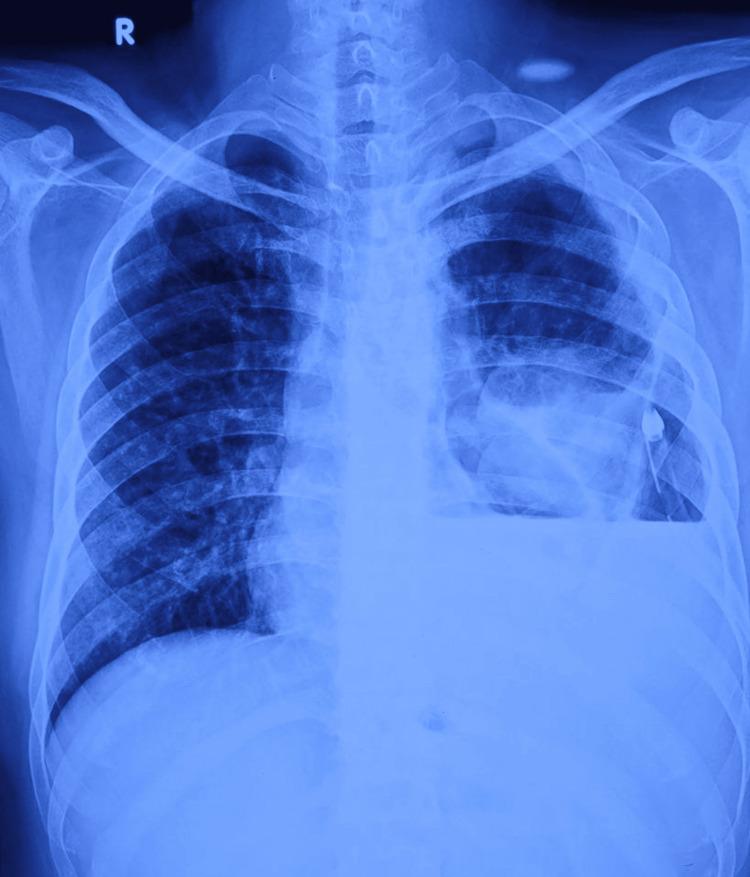

Nocardiosis is known as an opportunistic infection in immunocompromised hosts. We present to you a case of pleural nocardiosis in a 38-year-old male patient who was a chronic smoker and presented with a left-sided pleural effusion. He was a known case of thrombocytopenia due to immune thrombocytopenia (ITP) and was on steroid therapy. On admission, he was found to be positive for HIV. Pleural fluid was sent to microbiology, where acid-fast staining with 1% sulfuric acid (HSO)showed acid-fast branching filamentous rods and cultures grew which was resistant to ampicillin, ceftriaxone, imipenem, cotrimoxazole, erythromycin, tetracycline, and susceptible to amikacin, linezolid, and levofloxacin. The isolate was identified as using 16S rRNA gene sequencing. Culture from the chest wall drain grew and Subsequently, the patient developed sepsis, and paired blood cultures grew . Unfortunately, the patient could not survive despite aggressive efforts and died after 40 days of admission.